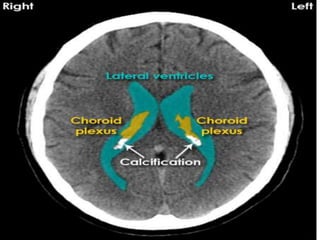

Density of various structures

Hyperdensities

• Blood.

• Clot

• Calcium.

• Prosthesis.

• Contrast uptake.

• Choriod plexsus calcification and bone are the

do main hyperdensities that are present in

normal CT.